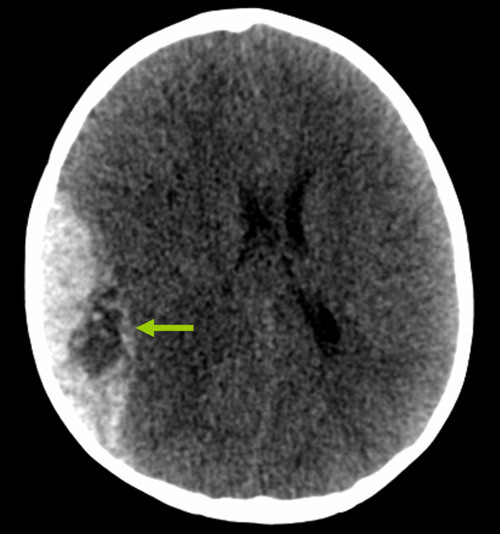

I akuttmottaket åpnet han så vidt øynene på sterke smertestimuli, laget kun enkelte lyder og hadde målrettede avvergebevegelser, dvs. Glasgow Coma Score 9 (pediatrisk GCS-versjon). Etter en rask klinisk undersøkelse ble det utført CT-undersøkelse av hodet. Den viste et stort epiduralt hematom på høyre side, med masseeffekt og midtlinjeoverskyting (bildet til venstre). Man så også det som blir kalt «swirl sign», som indikerer en pågående og kraftig blødning (grønn pil) (2). På vital indikasjon ble han tatt direkte til Nevrokirurgisk operasjonsstue, der det ble gjort en kraniotomi med evakuering av hematomet. Ny CT-undersøkelse av hodet dagen etter viste pene postoperative forhold (bildet til høyre).